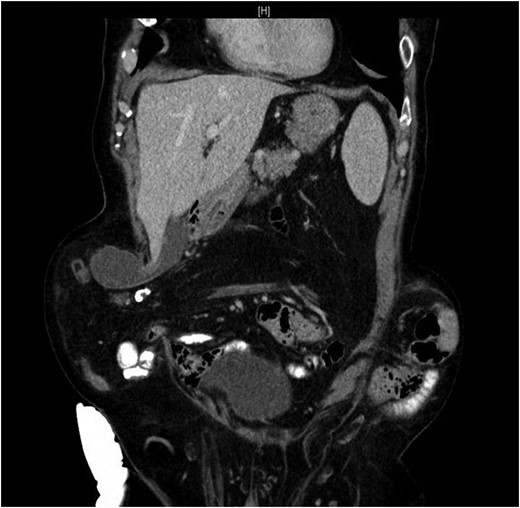

Our patient is an 89-year-old male with a history of a Hartmann’s procedure (2006) for Crohn’s disease of the sigmoid colon followed by a reversal of the colostomy with a diverting loop ileostomy (2008). Due to his comorbidities and age, the patient declined further surgery to reverse his loop ileostomy. Most recently, the patient presented to the emergency room with no ostomy output for the past 14 h, nausea and frequent burping. He reported a burning sensation around his ostomy. His physical examination revealed a large parastomal hernia in the right hemiabdomen and associated tenderness in the right upper quadrant, with no overlying skin changes. His white blood cell count was 8.1 (82.4% neutrophils), and he had normal liver function tests. A computed tomography (CT) scan of the abdomen and pelvis revealed a large parastomal hernia with a wide neck containing a distended gallbladder concerning for acute cholecystitis, as well as a small bowel obstruction with a transition point at the level of the hernia (Figs 1 and 2). A previous CT scan showed the same hernia with a nondistended gallbladder and non-obstructed bowel entering and exiting the stoma (Fig. 3).

CT from current admission with distended gallbladder consistent with acute cholecystitis.

Herniation of the gallbladder is rare, as demonstrated by this literature search. After a thorough review of the literature, we believe that this is the sixth reported case of a parastomal hernia that contains the gallbladder. However, this is the only reported case where acute cholecystitis resulted in a small bowel obstruction due to mechanical compression. Our patient had a distended gallbladder consistent with acute cholecystitis on CT scan when compared with a prior CT scan where the gallbladder was seen in the parastomal hernia, but without signs of distension or inflammation. The distended gallbladder was compressing the small bowel as it entered the parastomal hernia, resulting in a small bowel obstruction without any signs of ischemia. Of note, manual reduction of the patient’s hernia was not attempted in this case given the friability of the gallbladder secondary to acute cholecystitis and the potential for gallbladder rupture.